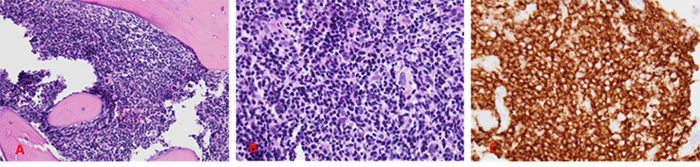

Bone marrow biopsy, performed as part of staging workup, revealed hypercellular marrow with reduced trilineage hematopoiesis and atypical B-cell infiltrates (Figure 2). Positron emission tomography (PET)/computed tomography (CT) scan identified mesenteric and external iliac lymphadenopathy along with focal bony involvement (Figure 3). The presence of atypical B-cell infiltrates in the bone marrow confirmed stage IV lymphoma by the Lugano classification.7

Figure 2. Bone Marrow Core Biopsy Findings. Published with Permission

A and B): Hypercellular marrow (90%) with increased infiltration of atypical lymphocytes (predominantly small with scattered intermediate and large cells) is seen on H&E staining (40x and 400x magnification, respectively). C): Immunostaining for CD20 highlights the atypical B cells